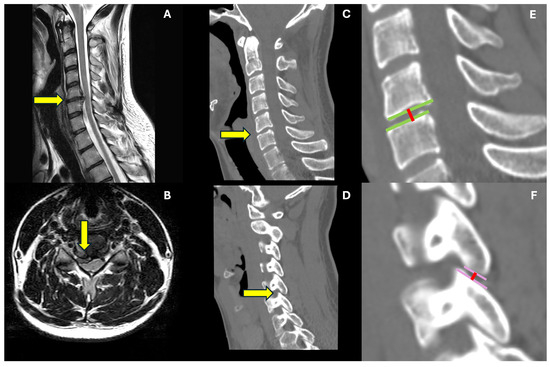

All patients were evaluated through a pre-operative cervical spine C.T. scan and MRI at admission. In contrast, a 1 month C.T. scan and cervical spine x-rays 6 and 12 months after surgery were required to assess radiological outcomes. Level of disc herniation was identified on the pre-operative MRI, while the disc height, defined as the distance between the upper and lower endplate measured at their middle point, the segmental zygapophyseal joint (ZAJ) distance, considered as the gap between the cortical rims of the joint measured at their middle point (mean measurement between the R and L distance), and global cervical lordosis were calculated on pre- and post-operative C.T. scans and x-rays, respectively. Cervical fusion was considered to have a Cobb angle variation < 4° and an interspinous process distance variation < 2 mm in dynamic x-rays or bone bridges on lateral view x-rays [22]. One single experienced spine surgeon (L.R.) performed all the measurements on the institutional picture archiving and communication system (PACS). Measurements are illustrated in Figure 1.

Figure 1.

Case illustration—radiological measurements. This is an illustrative case of a 32-year-old male suffering from C5-6 right paramedian cervical disc herniation, determining C7 radicular pain and triceps palsy. In (A,B), sagittal and axial t2-weighted 1.5 T MRI, respectively, we see identified by the yellow arrow the herniated disc and no significant degenerative condition of the rest of the cervical spine. In (C,D), we find the CT scan exam, including sagittal median (C) and lateral (D) cuts. The (E) is a zoomed image of the C5-6 level, where we illustrate how we measure di discal space height (red line) at the mean point of the opposite endplates (green lines). The (F) is a zoomed visualization of the zygapophyseal joint; in this the joint rims are identified by the pink lines, and the distance is measured at their mean point (red line).